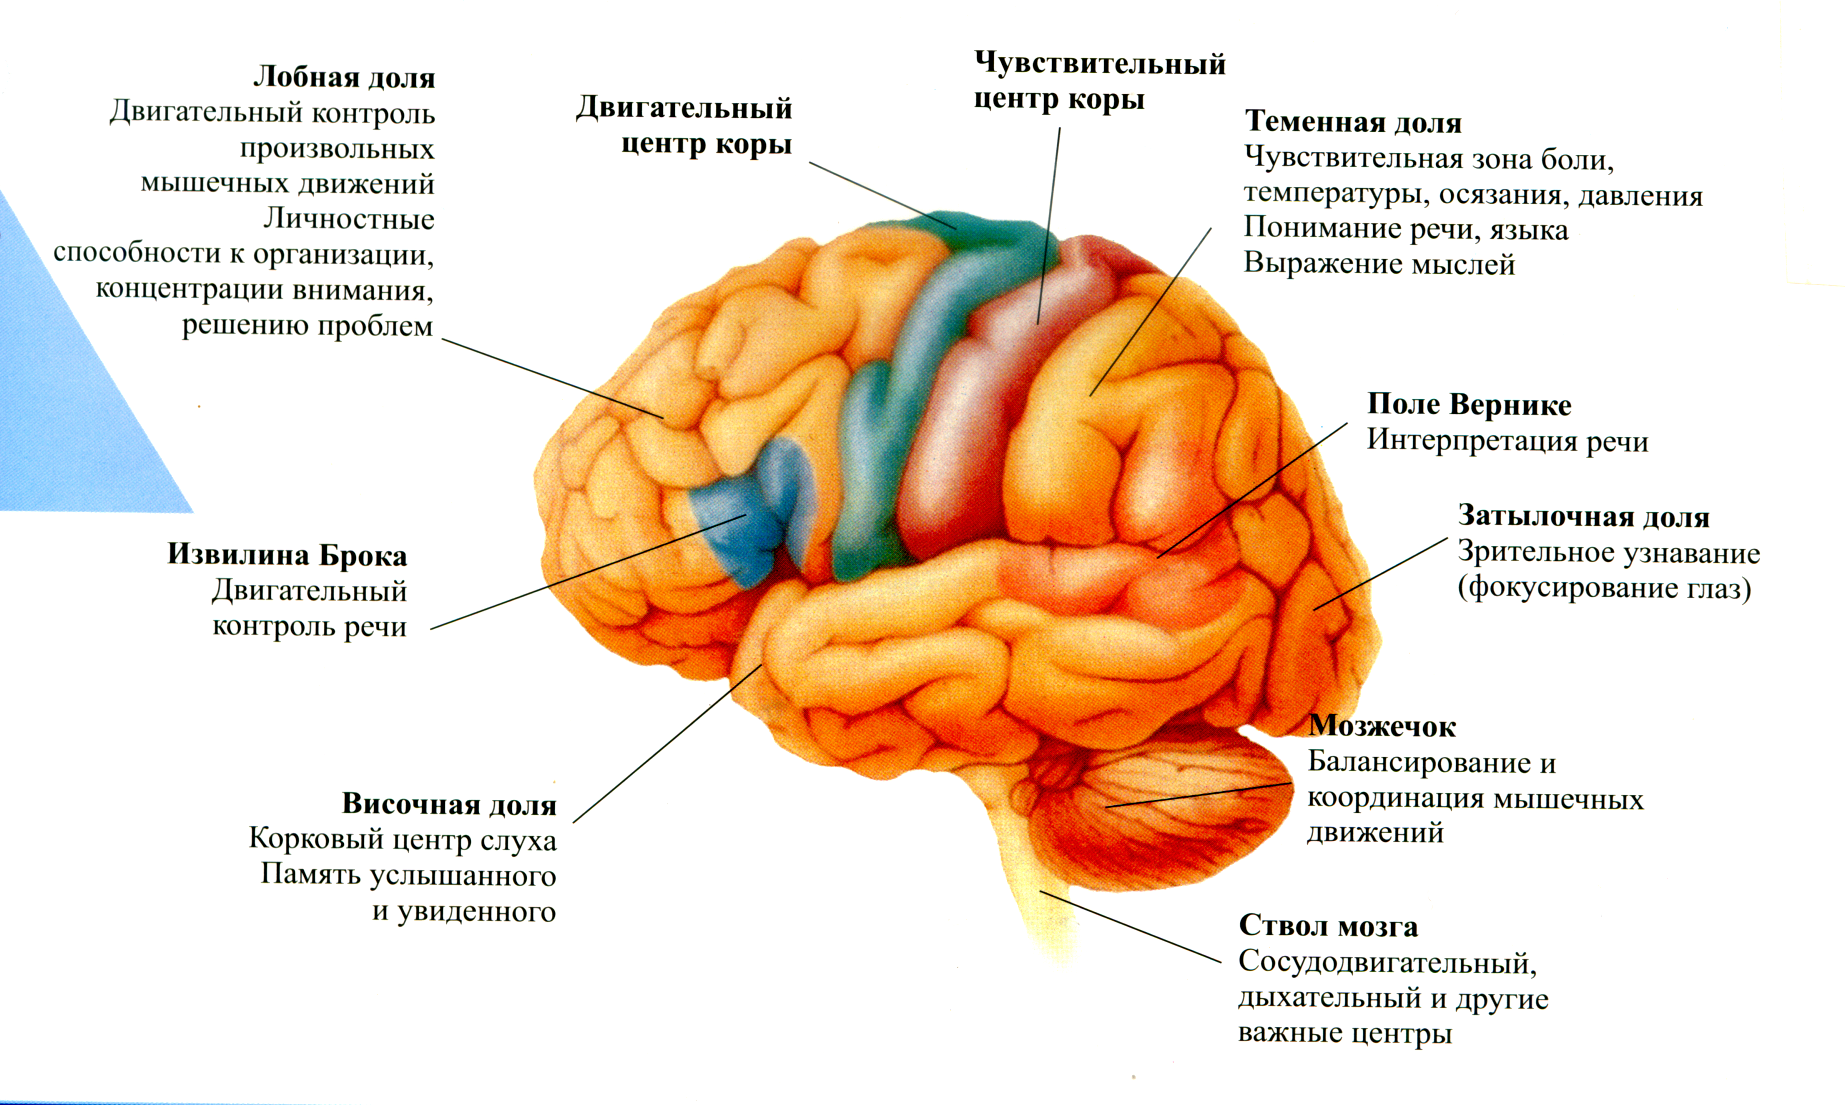

Как работает центр насыщения в гипоталамусе: визуальные иллюстрации